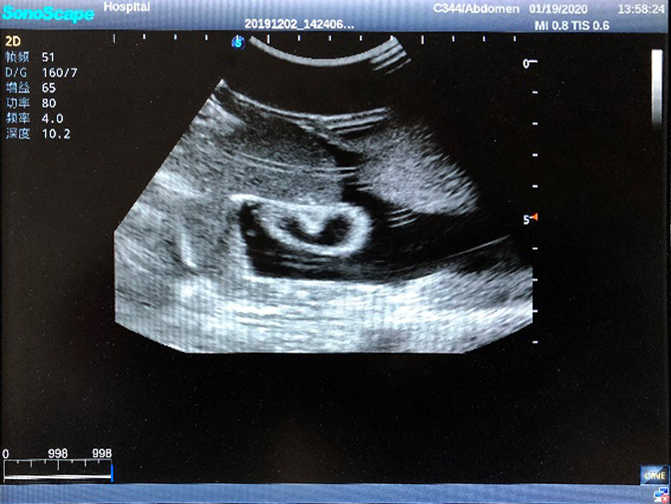

2)  High quality ultrasound image with clear structures like gallbladder, liver, intestines, arteries and veins etc.